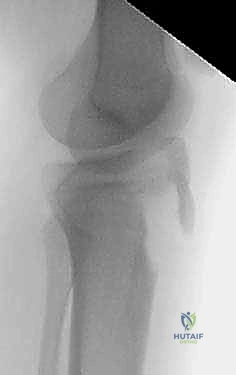

2. التصوير بالأشعة السينية (X-Rays)

هو الخطوة التشخيصية الأساسية. يتم أخذ صور من زوايا متعددة (أمامية خلفية AP، وجانبية Lateral). الصورة الجانبية هي الأكثر أهمية لأنها تظهر بوضوح مدى انفصال (انزياح) حدبة الظنبوب عن مكانها الطبيعي، وتظهر أيضاً ارتفاع الرضفة (Patella Alta).

- ارتفاع صابونة الركبة (Patella Alta): بسبب انفصال وتر الرضفة عن الساق، تقوم العضلة الرباعية بسحب الصابونة إلى أعلى الفخذ، مما يجعل شكل الركبة يبدو غير طبيعي.